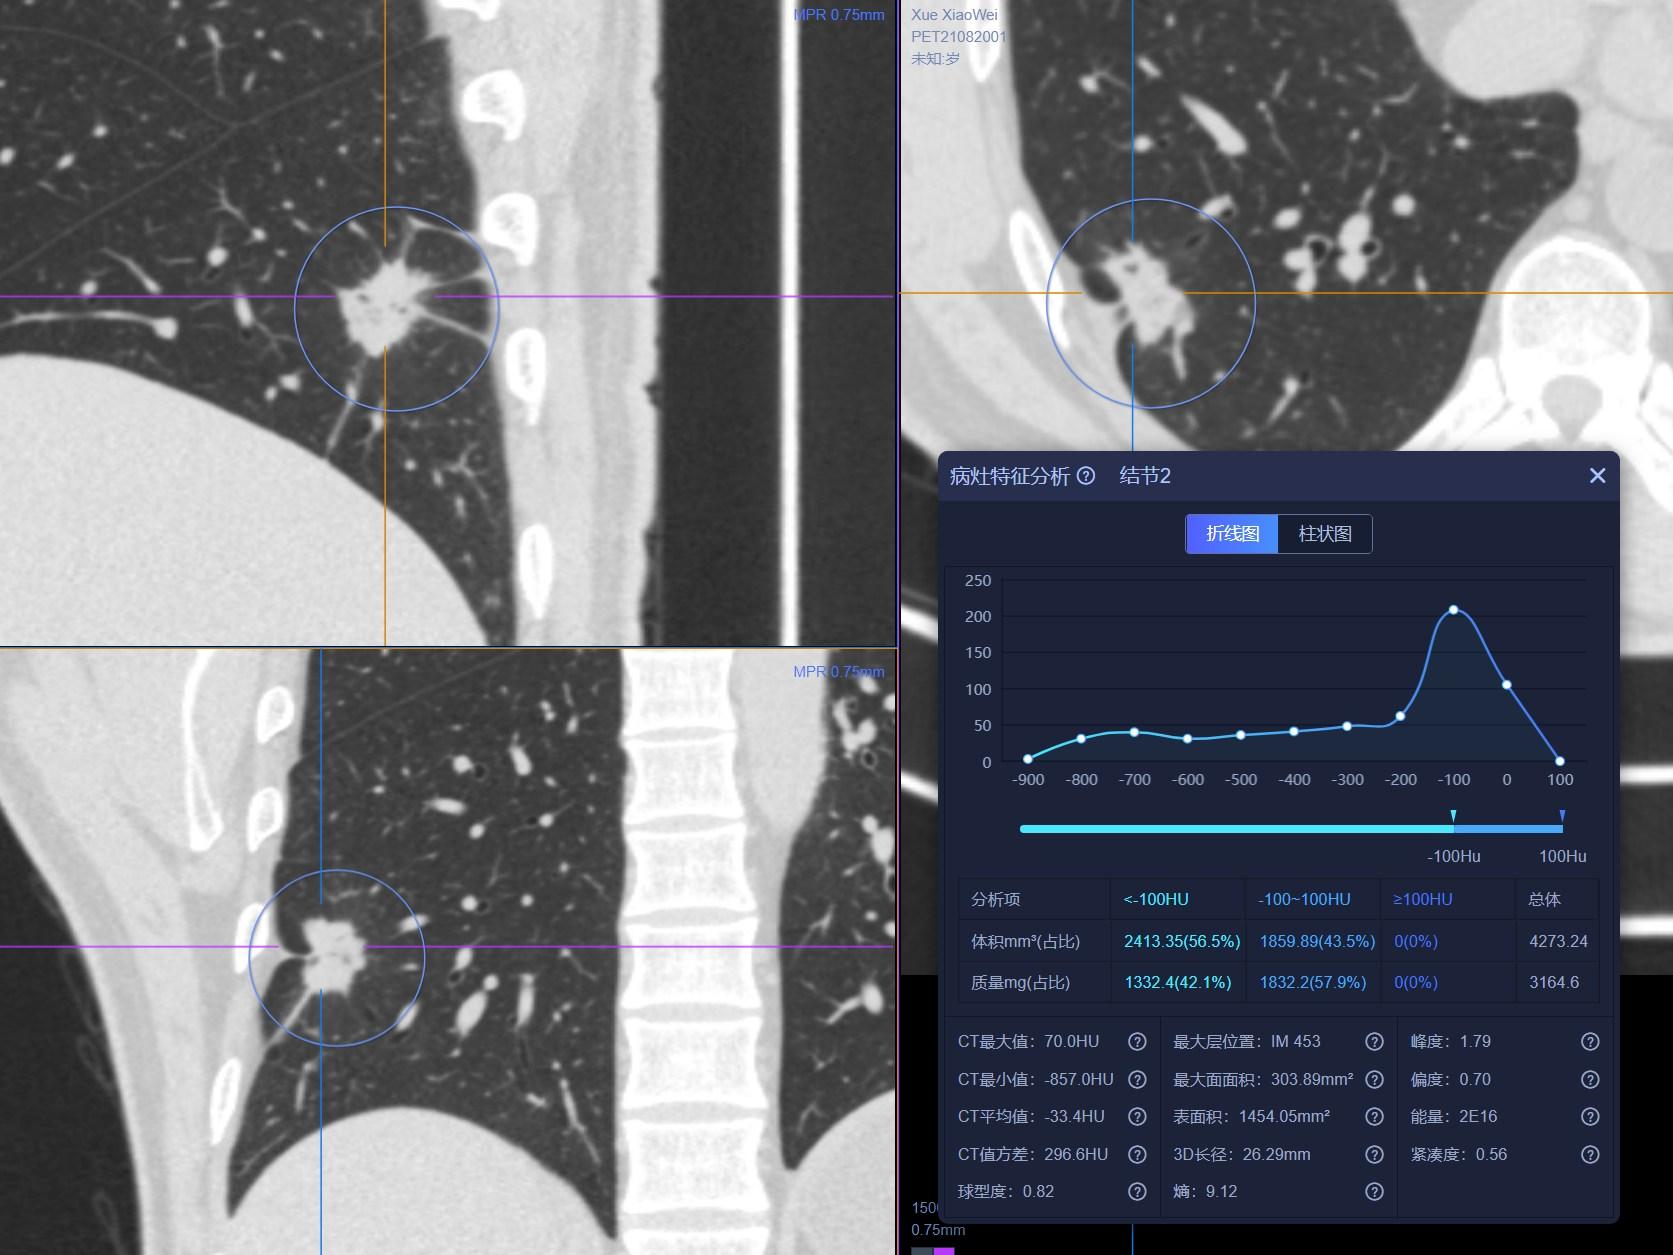

患者1:图1

经常看我科普及所有临床或者影像科医生对这个结节的诊断都没有什么怀疑,病灶大小约2.0cm×1.2cm,实性软组织成分,病灶呈分叶状,周边可见长短不一毛刺,并可见小空洞,相邻胸膜牵拉,全部是恶性征象。单单从CT诊断基本明确。

患者1:图2

另外,薄层CT还提示肺内还发现3个结节,从CT上诊断明确,考虑为纤维增殖灶。